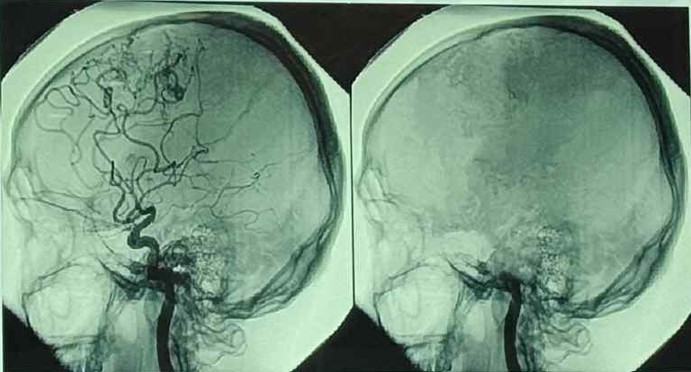

Жишээ нь, MRI оношилгоогоор эрүүл тархины зураг бол судас салаалсан цусны урсгалтай харагдана. Харин тархиы үхэлд орсон бол цусны урсгалгүй болсон байдаг. Давхар тархины цахилгаан бичлэгийн аппаратаар оношлоход эрүүл, сэтгэн бодож байвал цахилгааны бичлэгийн долгионууд нь далайцтай хэлбэлзэнэ. Тархины үхэлд хүрсэн бол ямар долгионгүй, зураас болж харагдана. Энэ мэт багажийн хэд хэдэн шинжилгээгээр оношилохын дээр мэргэжлийн багийн эмч нар нүд, чих, тархины болон залгих рефлексийг шалгах багажийн бус хэд хэдэн шинжилгээг хийсний дараа тархины үхэлд хүрсэн гэх эцсийн оношилгоо хийнэ. Эхний үзлэгээр дээрх шинжилгээнүүдээс ганц нь л эерэг гарвал тархины үхэл гэж үзэхгүй. Бүх шинжилгээний хариу сөрөг гарвал тархины үхэл гэсэн эцсийн онош тогтооно.